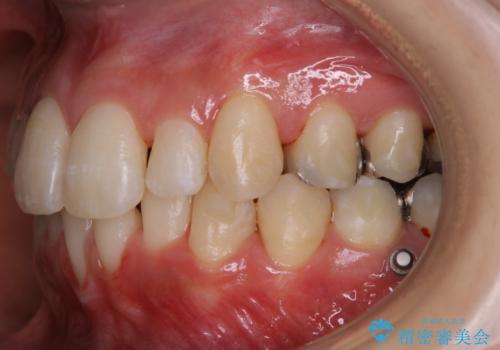

- 現在インビザラインでの矯正中で、歯の汚れが気になってきたためクリーニング希望とのことでした。PMTC60分コースを行いました。

PMTC(保険外治療)は、毎日の歯磨きで落としきれない汚れや、コーヒ、紅茶・タバコのヤニなどの着色も除去します。目には見えない歯と歯の間・歯肉の境目・インビザライン中はアタッチメント周囲などに残っているプラーク(歯垢)もしっかり取り除きます。PMTCでは専門的な機械や材料を使用して、徹底的に汚れを除去するため、虫歯・歯周病・口臭予防などにつながります。